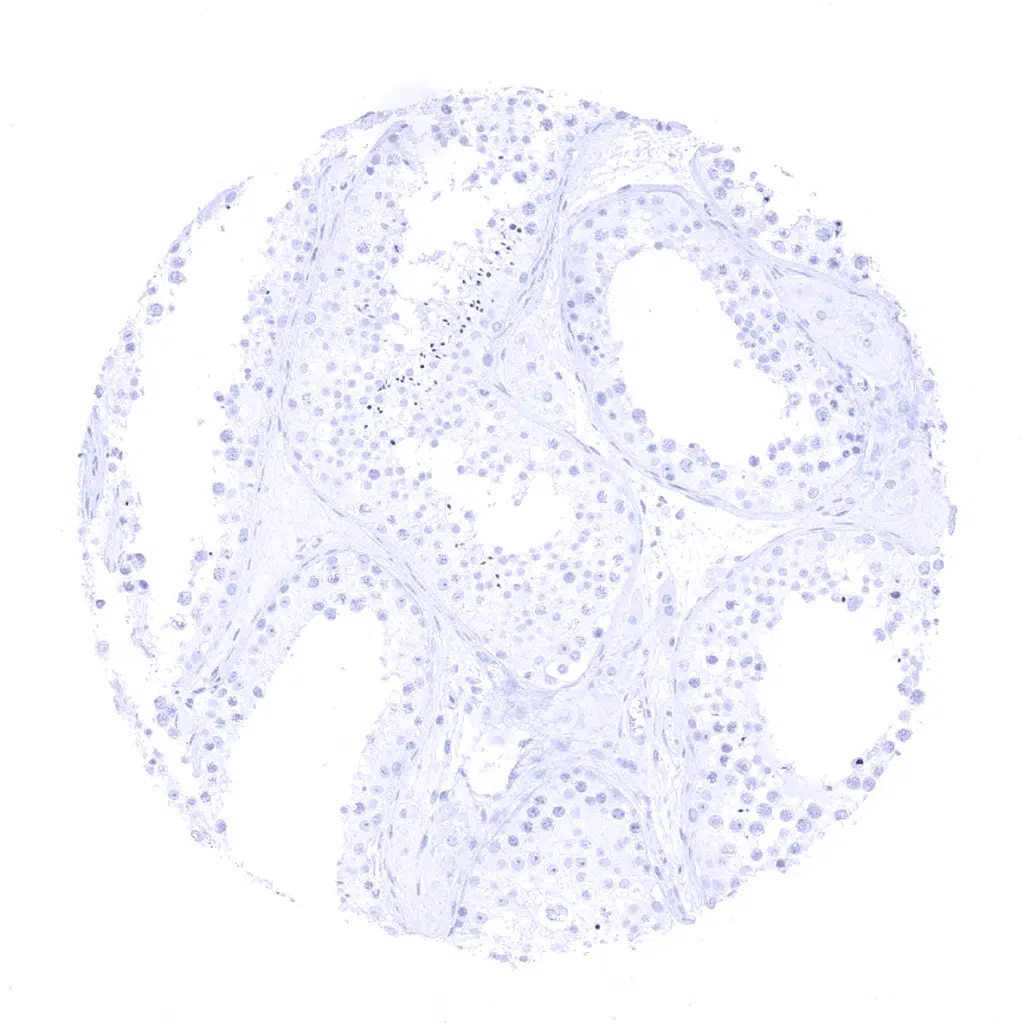

Prostate - A variable cytokeratin 19 staining intensity of both apical and basal cells can occur in the prostate but not in all glands and not in all samples.